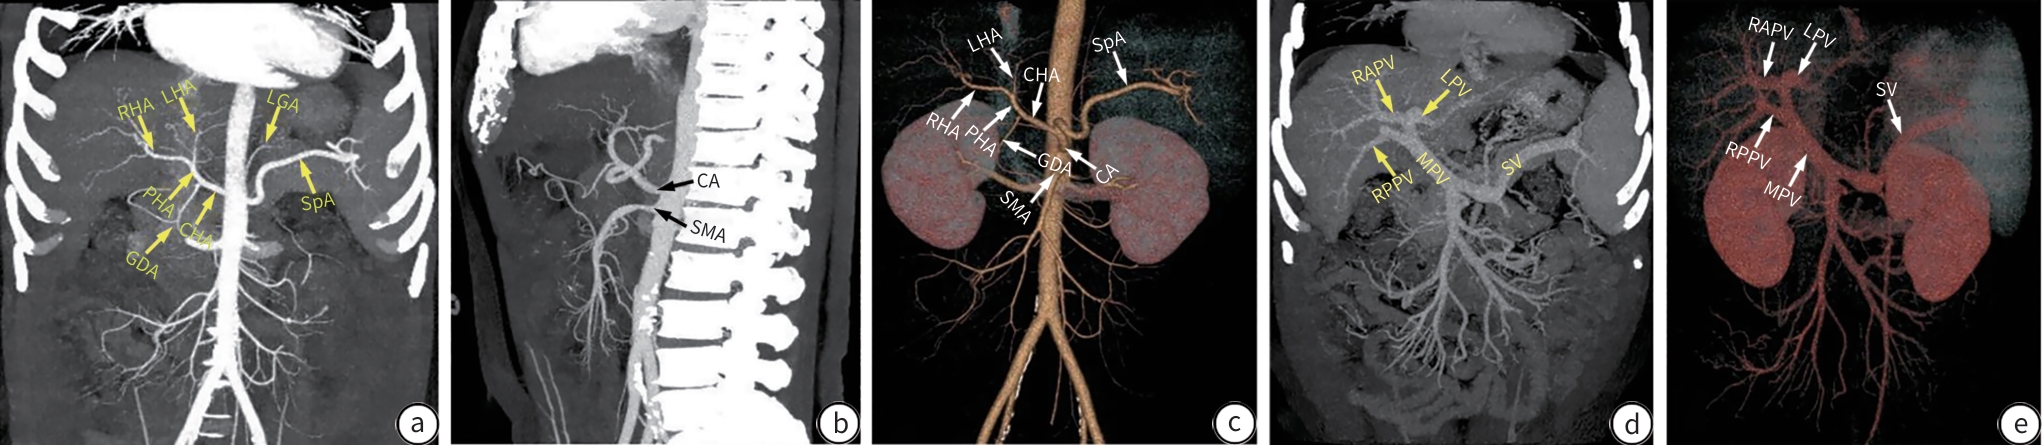

Expert consensus on clinical practice for the diagnosis and treatment of hepatic vascular diseases (2026 edition)

Committee on Liver Diseases (Integrated Traditional Chinese and Western Medicine), China Research Hospital Association, Committee on Interventional Medicine, China Research Hospital Association, Branch for Multidisciplinary Diagnosis and Treatment of Portal Hypertension, Beijing Medical Doctor Association

2026, 42(1): 47-65. DOI: 10.12449/JCH260107

Abstract(886) HTML (478) PDF (1269KB)(477)

Abstract:

Hepatic vascular diseases (such as portal vein thrombosis, porto-sinusoidal vascular disease, hereditary hemorrhagic telangiectasia, arterioportal fistula, and sinusoidal obstruction syndrome, Budd-Chiari syndrome) are characterized by diverse clinical manifestations, difficulties in diagnosis, and various treatment regimens, which brings huge challenges to clinical diagnosis and treatment, and at present, there are still no guidelines or consensus statements on the diagnosis and treatment of hepatic vascular diseases in China. To standardize and improve the diagnosis and treatment of hepatic vascular diseases in China, Committee on Liver Diseases (Integrated Traditional Chinese and Western Medicine) of China Research Hospital Association, Committee on Interventional Medicine of China Research Hospital Association, and Branch for Multidisciplinary Diagnosis and Treatment of Portal Hypertension of Beijing Medical Doctor Association organized the experts in related fields to develop expert consensus on clinical practice for the diagnosis and treatment of hepatic vascular diseases (2025 edition) based on the latest evidence-based medical research and the clinical practice in China, with a focus on the diagnosis and treatment of hepatic vascular diseases.